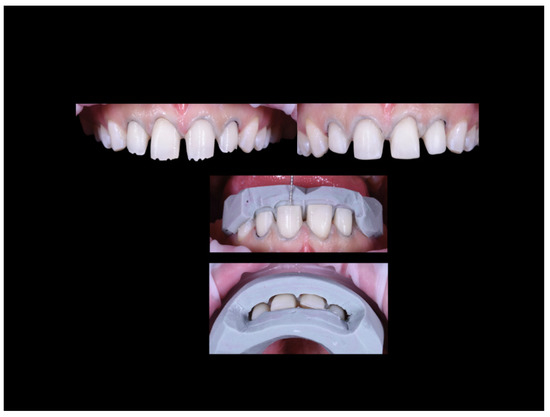

Case Report